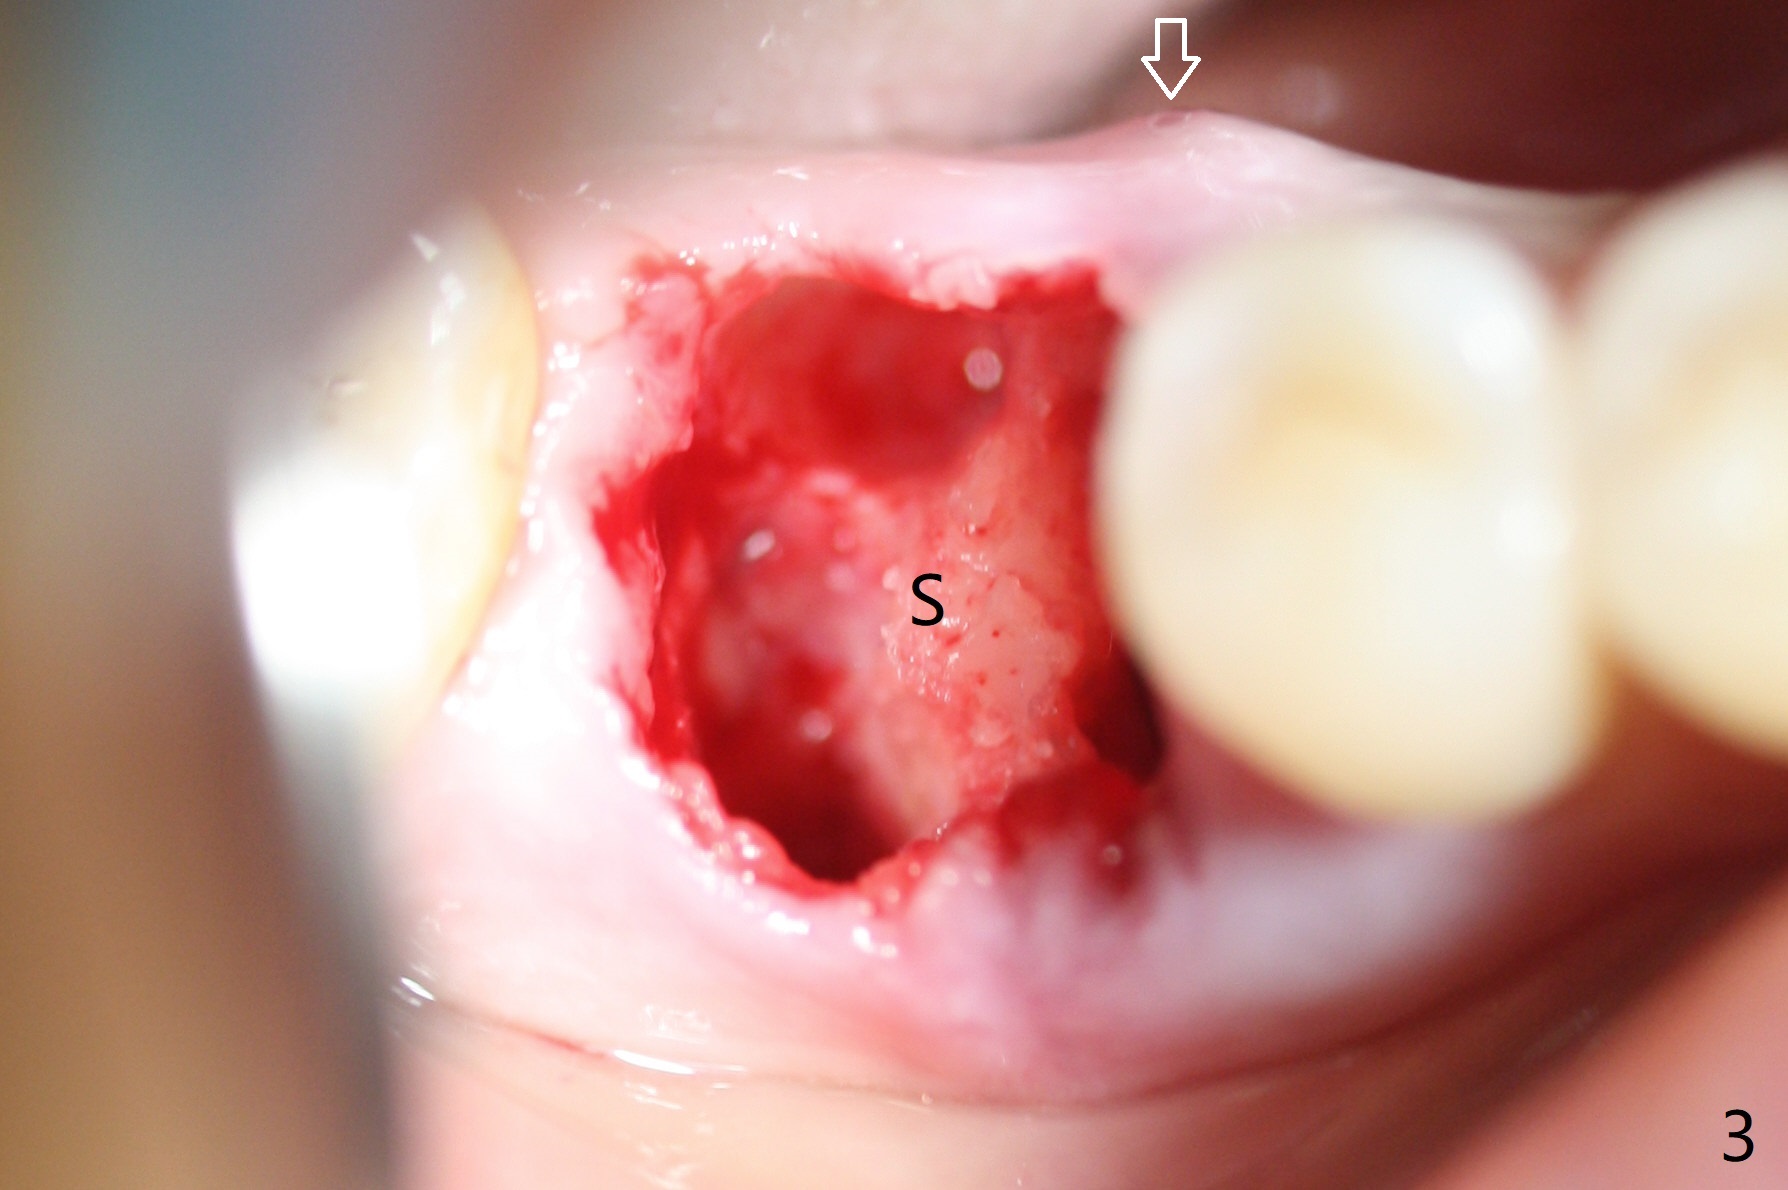

Preop oral Amoxicillin seems to be associated with reduction in the buccal and lingual (Fig.3 arrow) fistulae at #30, but there is mesiobuccal swelling (Fig.1 *) with 7 mm pocket (Fig.2). Osteotomy is initiated in the middle of the septum (Fig.3-5 S). As the osteotomy increases, it shifts mesially (Fig.6 arrow). Guided surgery is able to reduce shifting. A 5x13 mm implant is not seated completely (Fig.7) apparently due to osteotomy shifting. After removal of the bone from the osteotomy distally, the implant remains unseated with lower torque value (Fig.8). Following reuse of the 4.3 mm drill deeper by 1-2 mm, the implant is seated to a satisfactory depth (Fig.9 with increase in torque to 50 Ncm) with placement of Vera Graft (*) and a 7.5x4(3) mm abutment. After a second round of allograft placement (Fig.10 *), the implant is found to be 4 mm from the IAC. At the later stage of osteotomy, the coronal end of the septum is destroyed with loss of osteotomy depth landmark. It is apparent that the soft tissue landmark may be more reliable. The implant threads appear to be covered by the bone graft 3.5 months postop (Fig.11). The abutment is changed to 6.5x5(3) mm one before impression with minor margin prep. The bone density seems to increase 5 months postop, i.e., immediately post cementation (Fig.12) and 10 months postop (5 months post cementation (after retightening abutment), Fig.13 (*)). Periimplantitis develops mesiobuccally, consistent with bone loss 1 year 7 months post cementation (Fig.14 *); the implant seems to have been buccally placed. Bone graft is necessary with PRF or GEM21S if the vein is small and 6-month membrane with a hole around a 7.5x4(4) cemented abutment for easy wound closure. Take 5x5 CM CBCT to determine which wall has defect, buccal or lingual. Check mesial contact. If so, remove the crown, reseat the abutment (possible incomplete seating) and re-impress after bone graft.